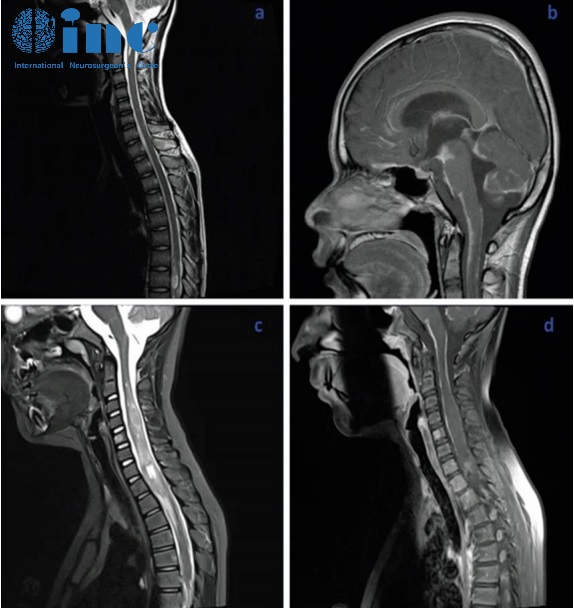

脊柱磁共振顯示腦膜彌漫性強化,腦膜覆蓋多處結(jié)節(jié)性病變,以及實質(zhì)內(nèi)病變和結(jié)節(jié)性小囊腫。

顱腦磁共振序列可見腦膜明顯強化,是腦干腹側(cè)表面上的軟腦膜。

小腦彌漫性可見多發(fā)囊性病變,特別是上葉正中區(qū)和上蚓部,可能導(dǎo)致腦脊液循環(huán)障礙伴繼發(fā)性腦室擴張。

從文獻中提取的一些圖像說明了剛才提到的情況:增強的蛛網(wǎng)膜的病理性增粗,腫瘤的多個結(jié)節(jié)狀定位,相關(guān)的腦積水。大腦的非強化局灶性囊性病變是由血管周圍間隙的局灶性擴大造成的,也是因為腦脊液循環(huán)受阻而擴大。

基于臨床的資料(年齡、性別、非不同性的神經(jīng)表現(xiàn)、腦積水)和神經(jīng)放射學影像(特征性的顱內(nèi)和椎管內(nèi)結(jié)節(jié)性腦膠質(zhì)增粗和強化,常伴有小囊性的非強化病變,蛛網(wǎng)膜下腔和室管膜表面的涂層),我可以確認彌漫性軟腦膜膠質(zhì)神經(jīng)元腫瘤的診斷。